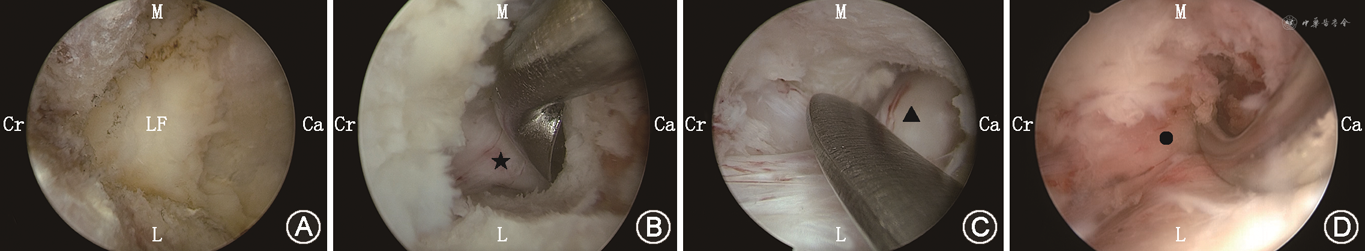

1.UBE组:患者全身麻醉俯卧位,通过C型臂透视定位,入路选择:根据患者是否伴有椎间孔狭窄选择,如伴有一侧椎间孔狭窄,则选择椎间孔狭窄对侧入路;如不伴有椎间孔狭窄则选择症状较重侧或根据医生习惯选择。切口设计:(1)左侧操作:后正中线旁开5 mm,下方切口位于下位椎板头端水平,上方切口以下方切口上移2.5~3.0 cm(根据患者脂肪厚度)为准;(2)右侧操作:后正中线旁开10 mm(右手为工作通道),切口水平位置较左侧略向尾侧移。观察通道的切口4~6 mm,工作通道的切口8~10 mm。逐级套筒抵至上位棘突椎板交界处尾侧,工作通道深筋膜做“十”字切开,逐级套筒扩张后,置入观察通道与工作通道。清理软组织后,在多裂肌三角内创建“初始营地”,依次切除上位椎板下缘、下关节突内缘、上关节突内缘及下位椎板上缘,游离黄韧带止点,暴露神经根的肩部及腋部,行同侧侧隐窝减压。减压满意后,沿黄韧带深层表面行对侧过顶减压,磨除对侧椎板腹侧及下关节突腹侧的骨质(3~4 mm),切除部分对侧下关节突腹侧面,暴露上关节突内侧缘,行对侧侧隐窝减压。若需行椎间孔减压,向头侧移动,切除上关节突尖部及椎间孔区黄韧带,充分暴露出行根并探查。减压满意后再次探查全椎管,确认减压满意后充分止血,内镜监视下置入引流管,固定。消毒,缝合切口,无菌敷料包扎后术毕(图1、2)。

注:Ca为头端;Cr为尾端;L为同侧;M为内侧;LF为黄韧带;★为同侧走行神经根;▲为对侧走行神经根;●为对侧出行根

ULBD是临床上常用的一种微创减压方式,通过单侧椎板切开实现椎管的双侧侧隐窝、椎间孔减压[18]。相较于开放减压手术,ULBD在术后疼痛、失血量、并发症率等方面有着明显的优势[7]。然而,在重度LSS中,由于椎管内空间狭小,在显微镜和单通道内镜下行ULBD存在技术难点,并可能存在减压不充分,并发症率升高等风险[17]。而UBE有着独立的观察-工作通道,无同轴管道的限制,器械操作自由,视野广泛,可视化强,可以使用大量开放手术器械,具有更高的减压效率[12, 13],可实现对全椎管的充分减压[15,19]。

本研究中,UBE组对比PLIF组,手术时间更短、出血量和术后引流量更少、术后下地时间和出院时间更早、花费更低,并且没有输血病例。UBE通过多裂肌下间隙创造操作空间,椎旁肌肉破坏小,并完整保存了后方韧带复合体,在充分减压的同时最大限度地保留脊柱稳定性,无需附加椎间融合以及内固定器械植入。相较与开放手术的裸眼减压,UBE术中能够辨认局部精细解剖结构及血管,通过有效的预止血以及静水压可大大减少出血。

关节突关节作为脊柱运动节段的一部分,破坏超过50%时,可能导致脊柱不稳[23]。UBE-ULBD治疗重度LSS的减压范围:水平方向上以两侧椎弓根内缘为界限;头尾方向上,头端通常减压至上位椎板腹侧黄韧带止点处,尾侧通常应减压至椎弓根中线水平,并应探查尾侧[24];在处理对侧椎间孔区域时,应切除上关节突的尖部及椎间孔区域的黄韧带,减压至椎弓根外缘[25],术中通过神经根探子探查,透视确定减压范围是否充分。在切除上关节突尖部时,应分块切除,切除应少于50%并保留关节囊,以尽量保留小关节的平移和旋转稳定性[26, 27]。